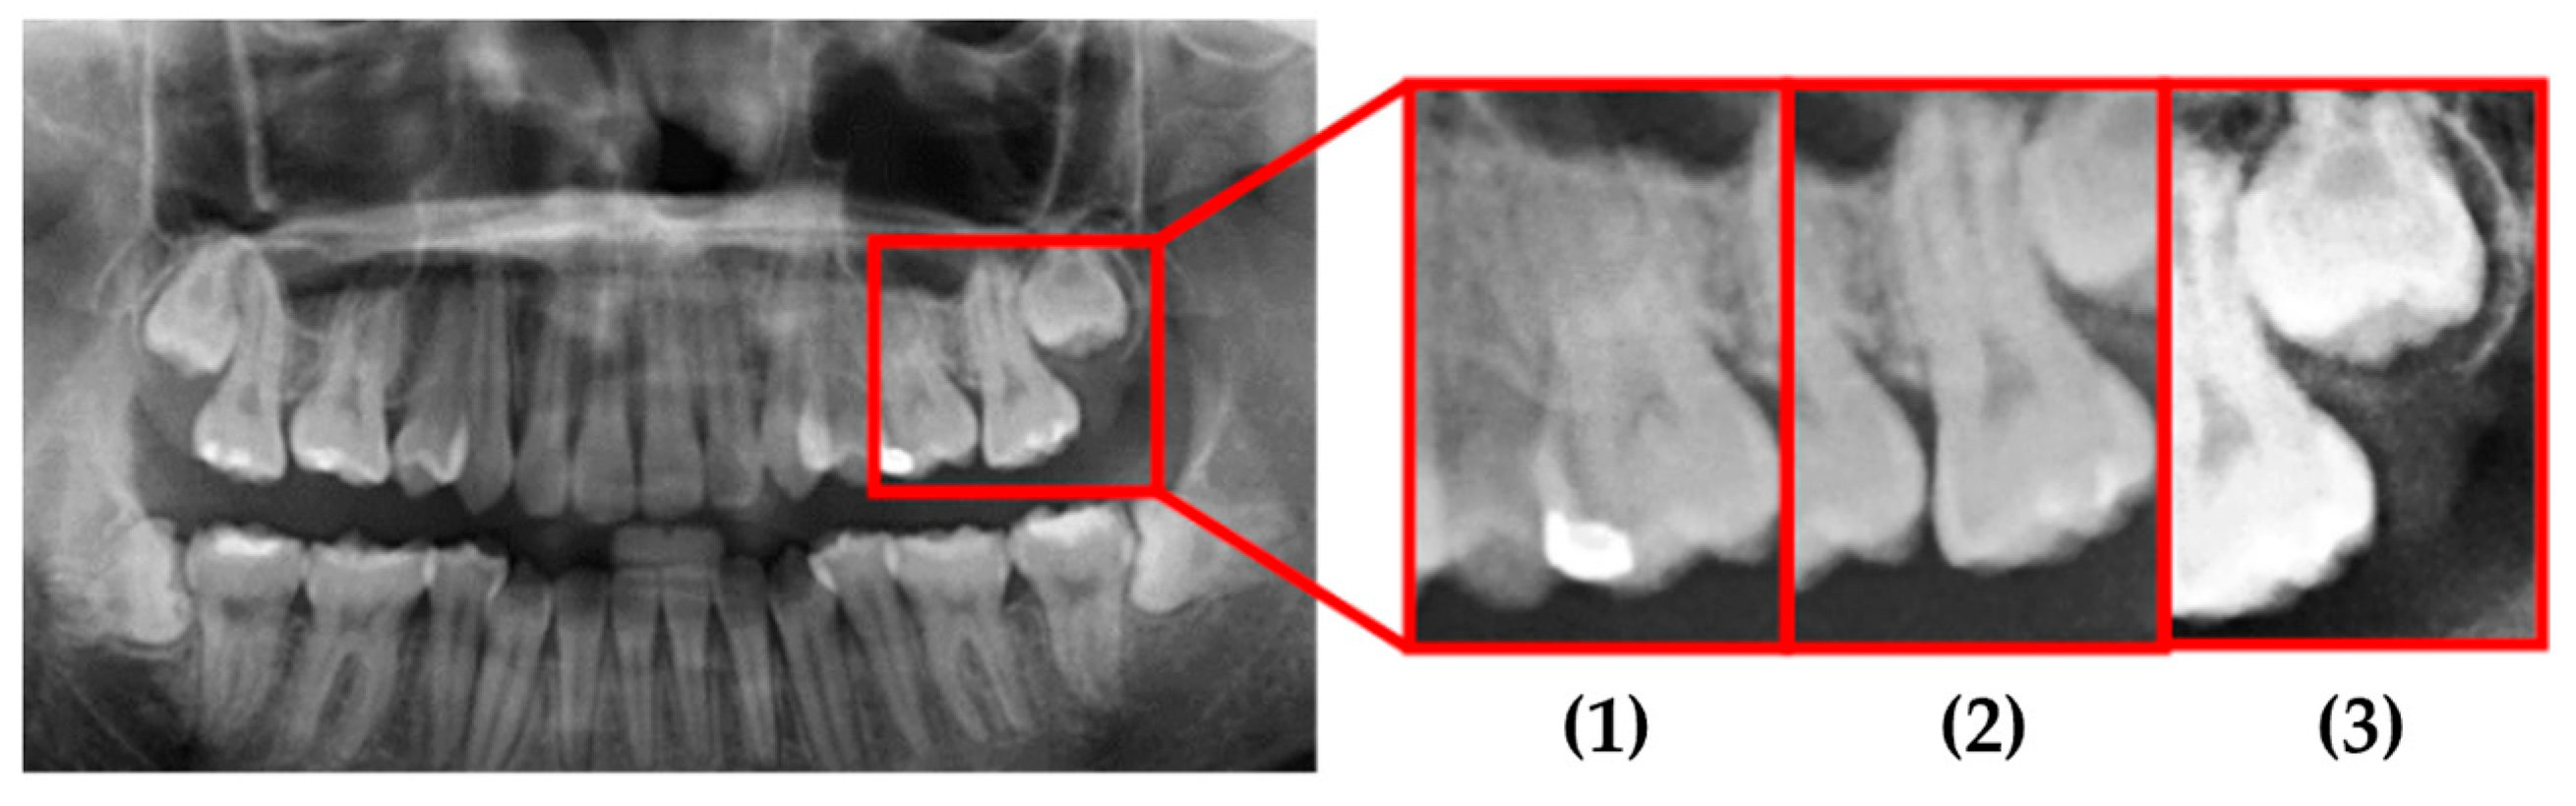

This study used actual clinical images, for example, as shown in Figure 17 and Table 7. When the original PANO image was input, it underwent image processing and cropping for calibration. Subsequently, image enhancement was applied to emphasize the symptom features. Finally, the enhanced image was fed into the CNN for classification. From the input of the original PANO image to the completion of identification, the process only took 4.4 s. Specifically, in this system, cropping the original PANO image into double-teeth images took 2.6 s, while image enhancement and CNN identification of impacted teeth took only 1.8 s. Image diagnosis through the final model approached the best results. Impaction was found to be correctly and quickly diagnosed with a high degree of reliability for each tooth.

Figure 17. Example data that was cropped by this study.

Table 7. The identified results by this study.

Tooth PositionOrigin DataThis Work

(1)Normal98.35% to be Normal

(2)Normal99.23% to be Normal

(3)Impacted99.87% to be Impacted